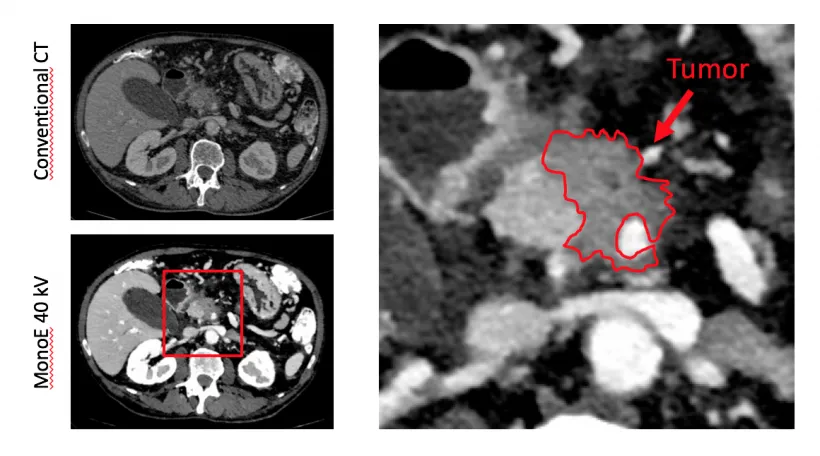

Wenn der Ultraschall keine eindeutigen Ergebnisse liefert oder weitere Details benötigt werden, kommen detailliertere bildgebende Verfahren wie die Computertomographie (CT) und die Magnetresonanztomographie (MRT), oft in Kombination mit der Magnetresonanz-Cholangiopankreatikographie (MRCP), zum Einsatz. Diese Methoden können strukturelle Veränderungen der Bauchspeicheldrüse sehr genau darstellen. Dazu gehören beispielsweise Anzeichen einer chronischen Pankreatitis (Entzündung der Bauchspeicheldrüse), die Erkennung von Zysten oder auch von Tumoren, die die Funktion der Drüse beeinträchtigen können. Diese bildgebenden Verfahren helfen also, die anatomischen Ursachen für eine EPI zu identifizieren.